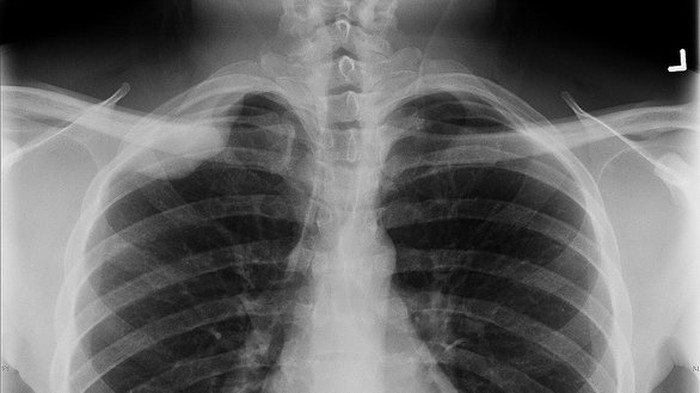

Dr Sarah Dalton dari Divisi Kesehatan Anak dan Dokter Anak Ikatan Kedokteran Australia mengatakan lebih dari 95 persen tindakan rontgen (x-ray) tidak berguna untuk anak-anak yang mengeluh sakit perut.

Untuk anak-anak yang mengalami kondisi keluhan di dada yang disebut bronchiolitis, hasil rontgen itu hanya berguna bagi 1 dari 100 anak-anak.

Dr Dalton mengatakan penting sekali para orang tua mengetahui bahwa rontgen di bagian perut menciptakan radiasi yang lebih besar dibandingkan rontgen di bagian dada.